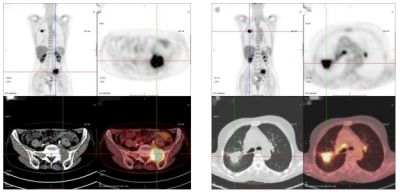

PET/CT顯像效果示意圖:腫瘤細胞對PET/CT顯像劑的攝取非常多,和正常組織相比異常“黑”所以顯示清楚。

66歲,女,左側腰骶部疼痛1月,ECT檢查示:胸7、骶1及左側髂骨多發骨代謝異常,考慮腫瘤性病變,轉移瘤?

PET/CT診斷:右肺上葉后段結節,代謝增高,考慮原發惡性病變(右肺上葉后段周圍型肺Ca)伴、肺內、淋巴結及多發骨轉移。